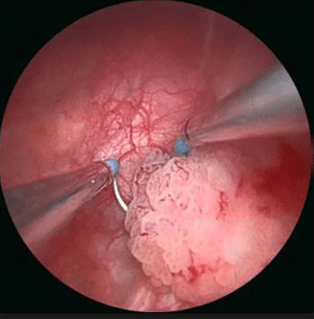

URETROCISTOSCOPIA

Consiste en la introducción de un Uretrocistoscopio a través del meato uretral y que permitirá la valoración de la uretra y de la vejiga. Aunque la mayoría de lesiones malignas vesicales son bastante bien reconocidas, el urólogo deberá tener alguna experiencia para determinar la presencia de lesiones sospechosas de Cáncer In Situ u otras lesiones menos comunes y benignas (Cistitis folicular, cistitis inespecífica, etc) que puedan ser causa de hematuria.

|

| En general, las lesiones malignas más frecuentes son fácilmente reconocidas sin embargo existen otras que pueden hacer dudar del diagnóstico. Es importante el estudio de imágenes en cistoscopia. |

RESECCION TRANSURETRAL DE VEJIGA

Una vez establecido el diagnóstico mediante Ultrasonido o Uretrocistoscopia, el siguiente paso es el abordaje quirúrgico.

La Resección Trans Uretral de Vejiga (RTU V) consiste en la exploración vesical bajo anestesia y la resección de la lesión sospechosa. Es un procedimiento que provee el diagnóstico histológico, grado y estadio clínico del tumor vesical y constituye la primera medida terapéutica que en algunos casos es definitiva.